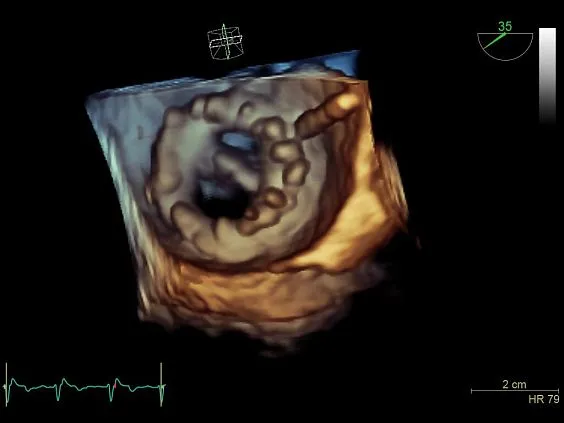

- 4D — режим 4D для ЧП датчика

- Advanced 4D — расширенный 4D-функционал

- 4D-MVQ Assessment — оценка митрального клапана для ЧП исследования.

- 4D-AVQ Assessment — оценка аортального клапана

- Бескомпромиссный уровень качества визуализации как в двухмерном режиме, так и в режиме объемной реконструкции, а также гарантируя высочайшую чувствительность при цветовом картировании кровотока и допплерографии.

- Беспрецедентное пространственное разрешение и детализацию.

- Auto LVQ — функция, которая дает возможность двумя нажатиями кнопок разместить точки исходных границ эндокарда, основываясь на данных, полученных от 4D TEE датчика. Данный инструмент количественного анализа позволяет отобразить в графическом виде полные 4D данные, используя технику трекинга поверхности на базе каркасной модели.

- 4D TEE — благодаря высокопроизводительной платформе cSound выполнение объемной чрезпищеводной ЭхоКГ стало ощутимо легче, понятнее и быстрее. Для вас открыты широкие возможности просмотра высокоточных изображений сердца во время оценки его функций и диагностики в условиях эхолаборатории, уверенное выполнение манипуляций под ультразвуковым контролем при катетеризации или инвазивных хирургических вмешательствах в операционной.